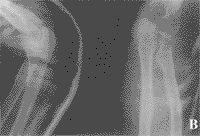

本组全部获随访,时间8~39月,平均24月。平均骨折愈合时间为7周,未发生骨折端再移位(封三附图)。两组疗效比较无显著性差异(P<0.05),见表2。

附图 尺骨鹰嘴骨折手术前(A)与手术后(B)X线正侧位片表现